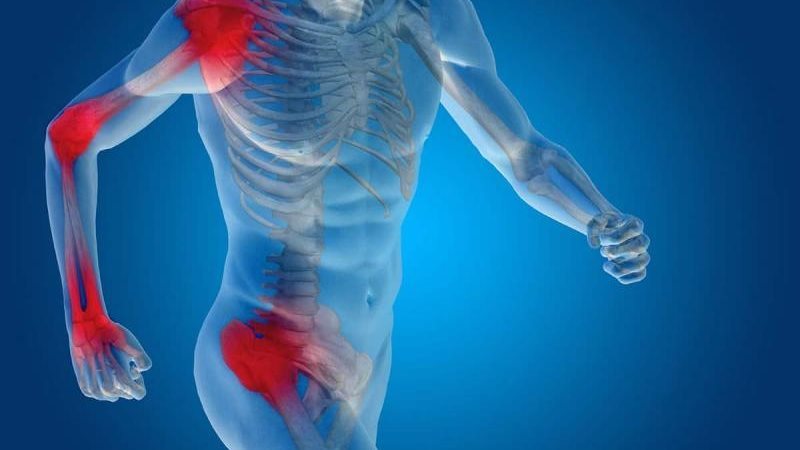

زيادة الالتهابات في الجسم من الأمراض الصامتة التي تسبب مضاعفات خطرة إذا لم يتم التنبه لها، وعادة تحدث الالتهابات نتيجة العادات الغذائية والحياتية الخاطئة.

وتحدث الالتهابات بالجسم نتيجة قلة النوم والإقبال على تناول الوجبات السريعة والسكريات ما يزيد الالتهابات بالجسم ومع الوقت تسبب الإصابة بأمراض القلب والسكر.

ويقول الدكتور أيمن ممدوح، أخصائي التغذية العلاجية، إن تقليل الالتهابات في الجسم مهم جدًّا للحفاظ على الصحة بشكل عام، لأن الالتهاب المزمن يمكن أن يسبب مشاكل صحية مثل أمراض القلب، والسكري، وآلام المفاصل، وهناك بعض النصائح التي تساعد في تقليل الالتهابات بالجسم، منها: